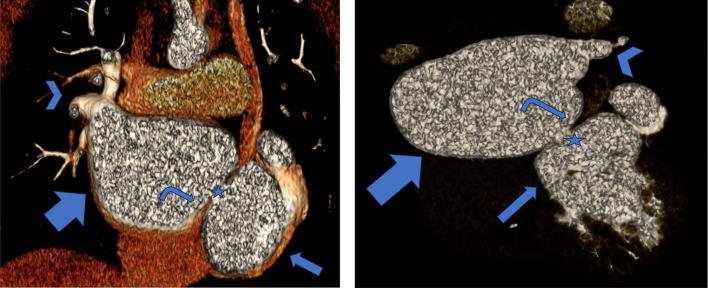

Cor triatriatum is an uncommon cardiac defect that occurs in 0.1-0.4% of congenital heart disease patients. It is characterized by a fibromuscular membrane separating the left (sinister) or the right (Dexter) atriums in tow chambers. The disease is usually discovered accidently in late childhood, usually as a result of a moderate form of this condition type. We discuss the case of a 14-year-old girl who had been experiencing exertional dyspnea and palpitations for about a year. She was referred to our hospital for assessment after an initial echocardiogram at another hospital revealed a mass around the left atrium. Repeated echocardiography at our institution revealed dilated coronary sinus, confusing the diagnosis. The left atrium was dilated and divided into 2 chambers by a thin membrane with an elevated pressure gradient between the 2 chambers. Cardiac CT and MRI confirmed the diagnosis of cor triatriatum sinister (CTS) with concomitant persisting left superior vena cava. Because of her symptoms, she was started medical treatment and referred for surgical evaluation. Cor triatriatum sinister (CTS) is frequently accompanied with atrial septal abnormalities and enlarged coronary sinus caused by a persistent left superior vena cava, as demonstrated in our case. The management of cor triatriatum sinister (CTS) is determined by the severity of the symptoms. Asymptomatic individuals with no pressure gradient do not require therapy; however, significant membrane obstruction may require surgical removal, which typically leads to positive short- and long-term outcomes.

三房心是一种罕见的心脏缺陷,在先天性心脏病患者中发生率为0.1%-0.4%。其特征是有一个纤维肌性膜将左心房(左位)或右心房(右位)分隔为两个腔室。该病通常在儿童晚期偶然发现,通常是这种病情的中度形式导致的。我们讨论一例14岁女孩的病例,她出现劳力性呼吸困难和心悸约一年。在另一家医院进行初步超声心动图检查发现左心房周围有肿物后,她被转诊至我院进行评估。我院重复进行的超声心动图检查显示冠状窦扩张,这使诊断变得复杂。左心房扩张,被一层薄隔膜分为两个腔室,两个腔室之间存在升高的压力梯度。心脏CT和MRI确诊为左位三房心(CTS)并伴有持续左上腔静脉。由于她的症状,她开始接受药物治疗并被转诊进行手术评估。如我们的病例所示,左位三房心(CTS)常伴有房间隔异常和由持续左上腔静脉导致的冠状窦扩大。左位三房心(CTS)的治疗取决于症状的严重程度。无症状且无压力梯度的个体不需要治疗;然而,明显的膜性梗阻可能需要手术切除,这通常会带来良好的短期和长期预后。